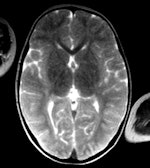

Le genre d'examen tomodensitométrique pratiqué sur un cadavre alimente les débats, et le travail de Mme Grabherr vise à augmenter l'usage de routine de l'angioscanner, ou angio-CT, un outil d'une grande valeur diagnostique, qui permet entre autres de fournir une cartographie détaillée du système vasculaire. La spécialiste a présenté les résultats d'une étude réalisée sur 45 corps humains en 2010, qui compare différentes techniques de perfusion utilisées lors d'un agioscanner post mortem, afin de soutenir le protocole suisse proposé (International Journal of Legal Medicine, novembre 2011, Vol. 125:6, pp. 791-802).

Dans une étude antérieure effectuée avec l'Institut de Médecine Légale à l'Université de Bern et publiée en 2008, la radiologue a montré comment la perfusion rétrograde du réseau veineux révélait des anormalités vasculaires, confirmant le diagnostic d'intoxication par drogues suspecté (American Journal of Roentgenology, février 2008, Vol. 190:2, pp. 345-351).

L'angioscanner améliore les études post mortem, en déterminant par exemple la source exacte d'une hémorragie. La procédure devrait être appliquée en routine pour les arrêts cardiaques subits, les décès par traumatisme et ceux survenant après une intervention médicale, recommande Mme Grabherr.

La technique d'angio-CT post mortem en phases multiples développée par les instituts suisses utilise une pompe construite sur mesure, et qui assure que les volumes d'agent de contraste sont assez élevés pour irriguer complètement le système vasculaire. Après avoir travaillé sur deux versions prototypes avec la société Fumedica, la troisième génération a fait son entrée sur le marché en septembre dernier, toujours selon l'experte.

Le président de la séance, M. Fabrice Dedouit, docteur au Centre Hospitalier Universitaire de Toulouse, et M. Mangin ont donné une vue d'ensemble des technologies de pointe pour ce secteur en plein développement, insistant sur les avantages d'un examen non destructif face à l'autopsie traditionnelle. L'autopsie virtuelle utilisant le scanner offre une alternative crédible en cas d'objection religieuse ou culturelle à l'autopsie chirurgicale, ou bien lorsque ouvrir un corps présente un danger potentiel, par exemple chez des victimes d'un acte possible de bioterrorisme. Les preuves existent qu'une étude visuelle des gaz emboliques, qui disparaissent une fois le corps ouvert, peut également permettre de déterminer les causes du décès et les méthodes employées pour y parvenir.